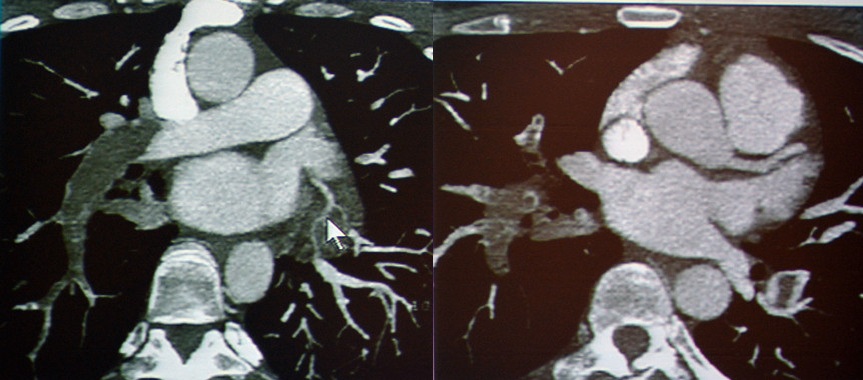

急性冠脉综合征:TRO可清晰地显示斑块、狭窄、闭塞和心肌缺血等病变。

图2-3 急性冠脉综合征